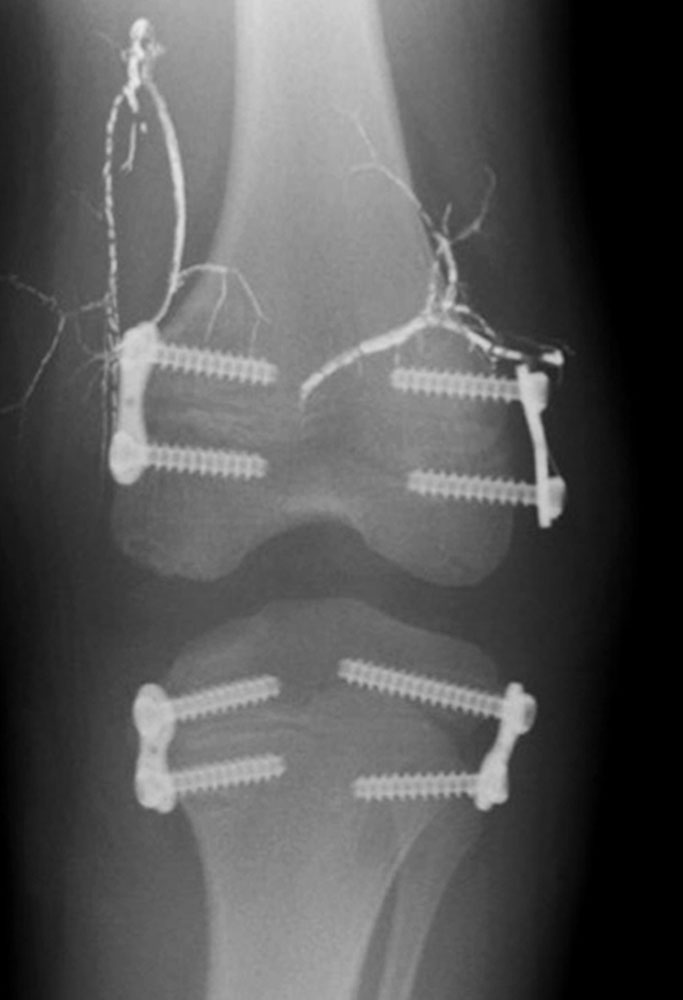

Temporary epiphysiodesis is achieved by temporary placement of metallic implants (e.g., clamps, plates, or screws) in the area of the growth plates, which can be removed after a certain period of time. Although there are a number of implants for this operation, they all have the same principle, in which the growth plate is firmly bridged (“stapled”) and thus growth is inhibited .

This surgical procedure makes it possible to compensate for a leg length over a defined period and then allow the treated limb to continue to grow by removing the implants. In many cases, however, epiphysiodesis must then be performed again shortly before growth completion to compensate for residual discrepancies.